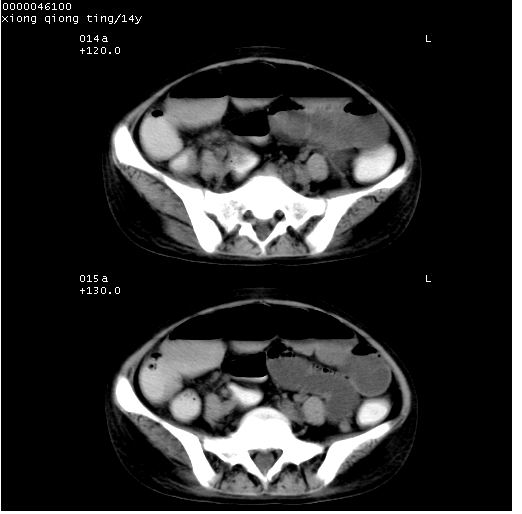

患儿 女,14岁。不规则发热一周,偶感头痛,无抽搐及呕吐。pe:神清,精神差,双侧瞳孔等大等圆,对光反射敏感,双肺未闻及明显啰音,心音有力,腹部触之似揉面感,下腹压痛,无反跳痛。

腹部b超提示:子宫缩小,盆腔积液,肝实质回声密集。

临床诊断:发热原因待查:1)腹部结核感染。2)伤寒?3)结缔组织病?

中下腹及盆腔ct轴位平扫+增强扫描(层厚10mm,螺距1.0,重建间隔10mm),图像如下:

(注:患儿检查当日上午9时口服胃肠道对比剂,下午3时许行ct扫描检查,未行对比剂直肠保留灌肠,检查当日患儿腹泻)

中下腹及盆腔ct轴位扫描(ps+ce)提示:腹部肠管明显充气扩张,并见数个不同宽度之气液平面;疑不全性肠梗阻或肠郁张。临床会诊考虑为患儿腹泻,肠郁张所致;后来未经特殊处理,患儿大便恢复正常,亦无腹胀。

临床出院诊断:1)结核性腹膜炎。2)腹膜后淋巴结结核。3)脂肪肝。